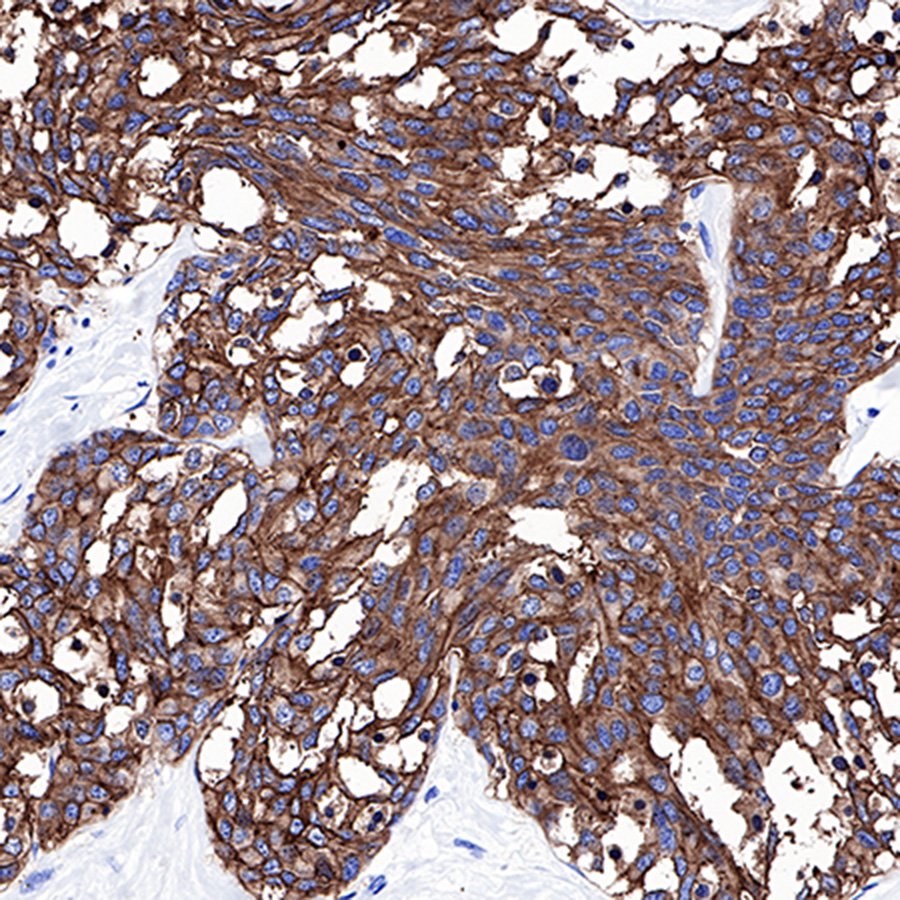

IHC shows positive staining in paraffin-embedded human colon cancer. Anti-CEA(CD66e) antibody was used at 1/1000 dilution, followed by a Goat Anti-Rabbit IgG H&L (HRP) ready to use. Counterstained with hematoxylin. Heat mediated antigen retrieval with Tris/EDTA buffer pH9.0 was performed before commencing with IHC staining protocol.